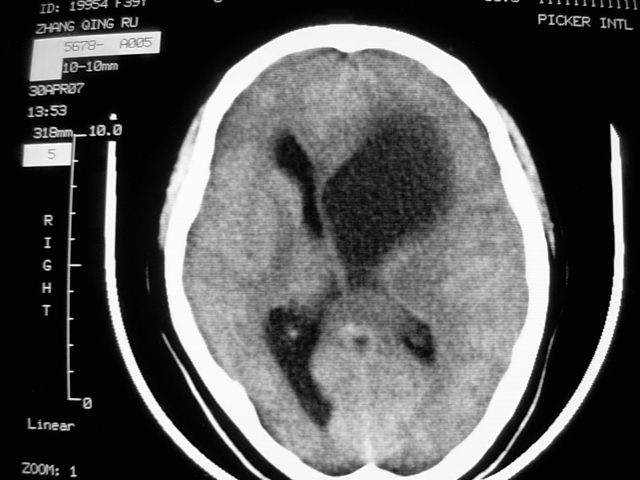

f39y,头疼、眩晕。患者拒绝强化。

左侧脑室增大,前角明显,中线向右移位,左侧脑室内见一肿块,密度不均,1室管膜瘤?2脑囊虫?

左额叶见一巨大椭圆形略低、低密度混杂密度肿块,边界清楚,似与侧脑室额角相通,明显占位效应,左侧侧脑室受压变形,右侧侧脑室扩大,中线结构向右明显弧形移位。鞍上池闭塞。

考虑:1、左额叶良性占位性病变,以皮样囊肿可能性大,伴镰下疝。

左侧脑室增大,前角明显,中线向右移位,左侧脑室内见一肿块,密度不均,内见钙化,1室管膜瘤?2脑囊虫?

类圆形低密度病灶与脑室内密度明显有差别,考虑:低密度病灶压迫四脑室形成的特殊影像。支持:皮样囊肿。

感觉病灶位于侧脑室前角内,而体部受压,病灶形态同前角一致,右侧脑室前角变形并不太严重,病灶呈混杂密度,考虑皮样囊肿或室管膜瘤可能性大一些。